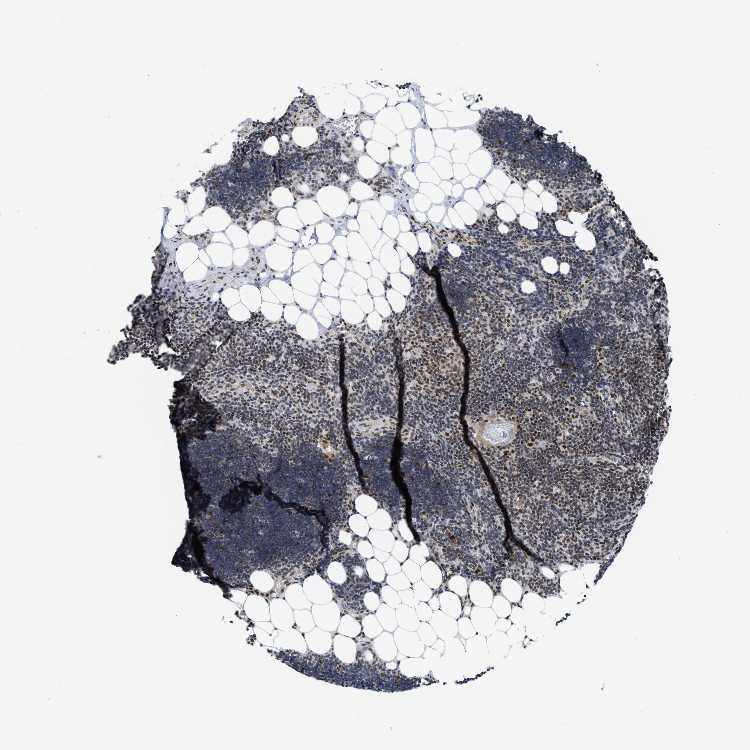

TISSUE PRIMARY DATA LYMPH NODE Show tissue menu

Lymph node

Lymphoid tissue

LYMPH NODE - Expression summary

LYMPH NODE - Antibody stainingi

Antibody staining in the annotated cell types in the current human tissue is reported as not detected, low, medium, or high, based on conventional immunohistochemistry profiling in selected tissues. This score is based on the combination of the staining intensity and fraction of stained cells.

Each image is clickable and will lead to virtual microscopy that enables deeper exploration of all samples and also displays staining intensity scores, fraction scores and subcellular localization as well as patient and tissue information for each sample.

Antibody HPA019589

Non-germinal center cells Medium